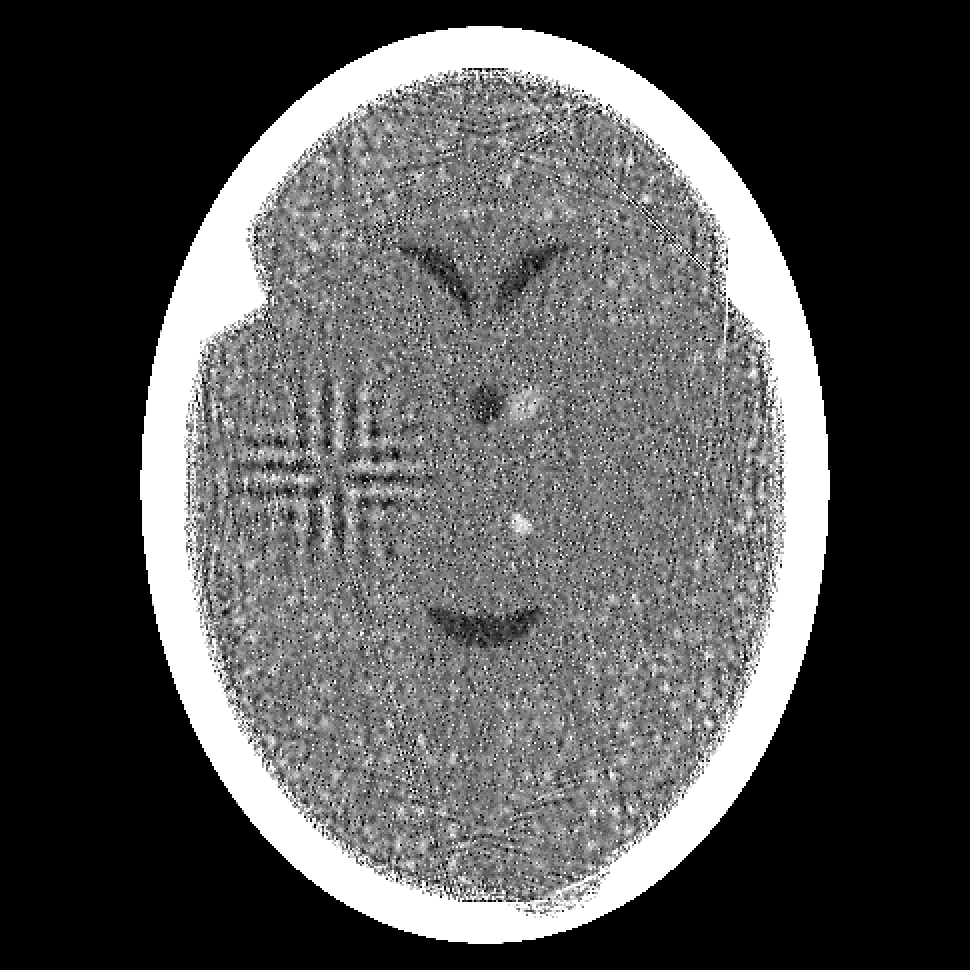

Figure 2: Reconstructions from 180 projections by (a) filtered back-projection, (b) the algorithm ART, (c) TV-Based Superiorized Version of ART, and (d) Shearlet-Based Superiorized Version of ART.

For this anecdotal experiment we use three different numbers of views (i.e., projections): 180, 360, and 720. We emphasize that, in the currently-described anecdotal experiment, there is only one phantom (which provides the ground truth); random generation of local inhomogeneities and of tumor locations is done only once and the same arrangement of local inhomogeneities and of tumor locations is used when generating the projection data for the three different numbers of views.

We present the visual results of the reconstructions produced by these algorithms when using 180, 360, and 720 projections in Figures 2, 3, and 4, respectively. We now give our impressions based on these visual results.

From the results for the single data set with 180 projections (Figure 2), we see that none of the four reconstruction algorithms produces an image in which the small tumors are easily locatable. Furthermore, the Shearlet-Based Superiorized Version of ART introduces high frequency artifacts in the brain near the skull and blurs the features inside the brain. In comparison, both filtered back-projection and ART (to a lesser extent) introduce artifacts in the form of streaks originating from interior bone edges. The image produced by TV-superiorized ART does not show significant high-frequency artifacts, the only one of the four, but the image is blurred.